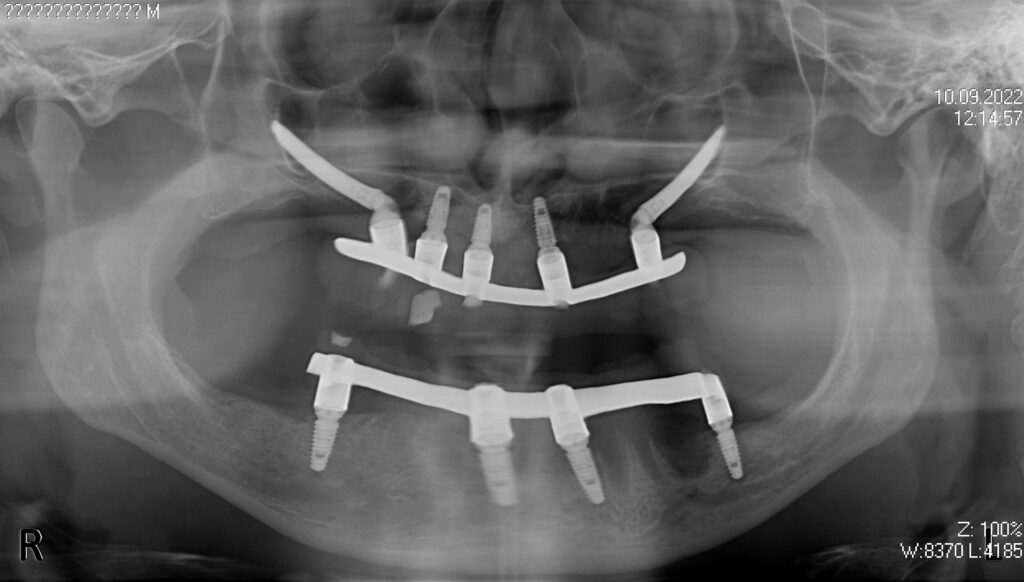

На верхней челюсти была проведена комплексная имплантация по системе All-on-5,

установлены 3 имплантата Megagen AnyOne и 2 скуловых имплантата NeoDent.

На нижней челюсти были установлены 4 имплантата Megagen AnyOne.

Спустя 7 дней на верхней и нижней челюстях зафиксированы металлоакриловые протезы из 12 зубов.

снимок

работы врача